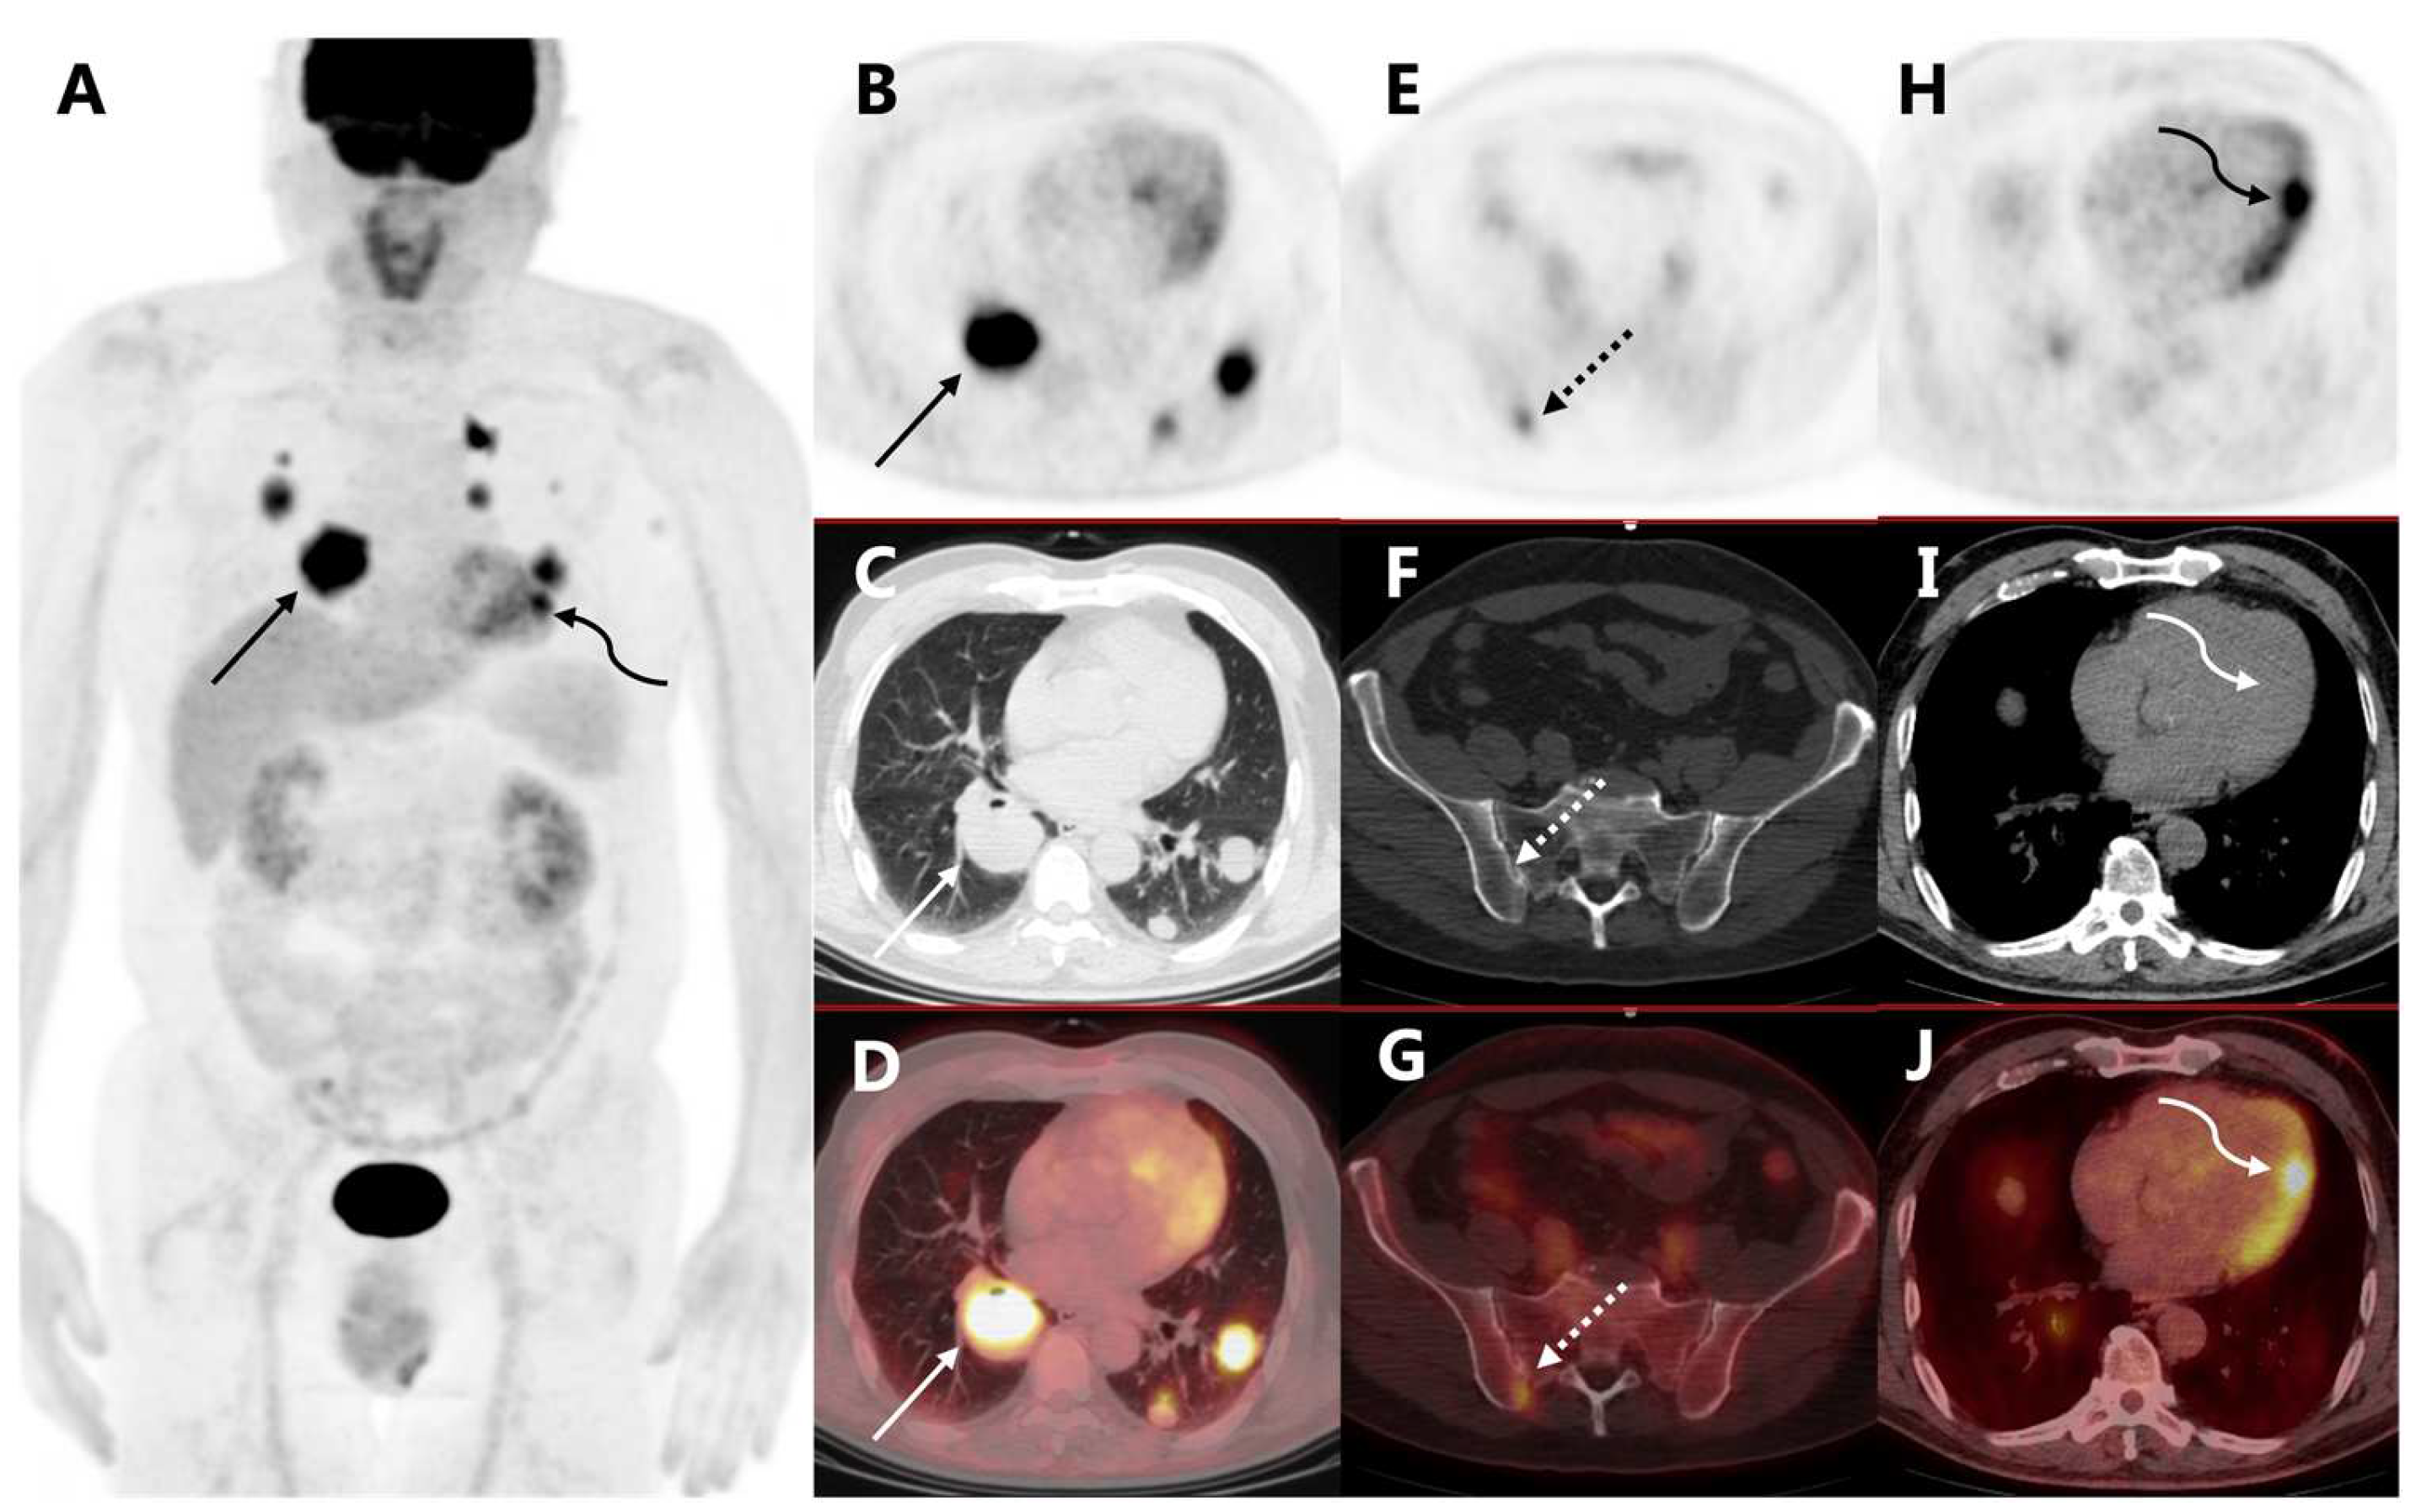

Cardiac Metastasis of Malignant Melanoma Detected by 18F-FDG PET/CT